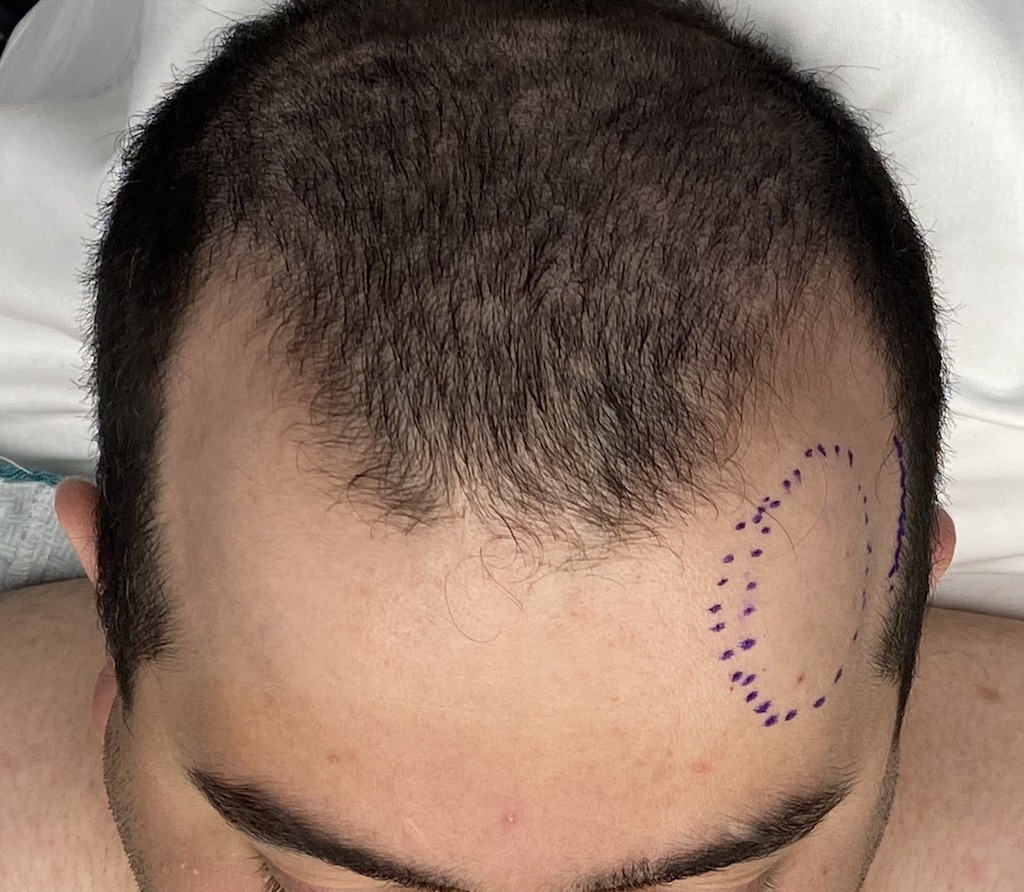

Desire for an improved head shape so that it looks rounder and not so peaked or sloped.

Placement of custom skull implant for parasagittal augmentation to create a rounder head shape. An example of what appears to be a high sagittal crest that is really low parasagittal skull areas.